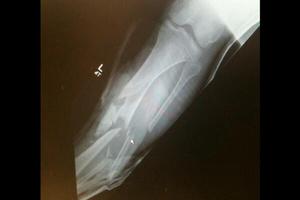

但在一周之後的British Supersport Championship賽事中, 由於地面濕滑, 發車不就後多名車手相繼倒地, 包括哈欽森. 不幸的是哈欽森倒地後, 後面的車手躲避不及直接撞到他的腿部, 造成左腿脛骨和腓骨完全斷裂.

哈欽森腿部傷情這場事故幾乎終結了他的賽車生涯, 醫生一度建議截肢. 但哈欽森堅持要求保留傷腿並決心重返賽場. 在16次手術和皮膚移植後, 哈欽森保住了左腿但錯過了多場重要賽事.